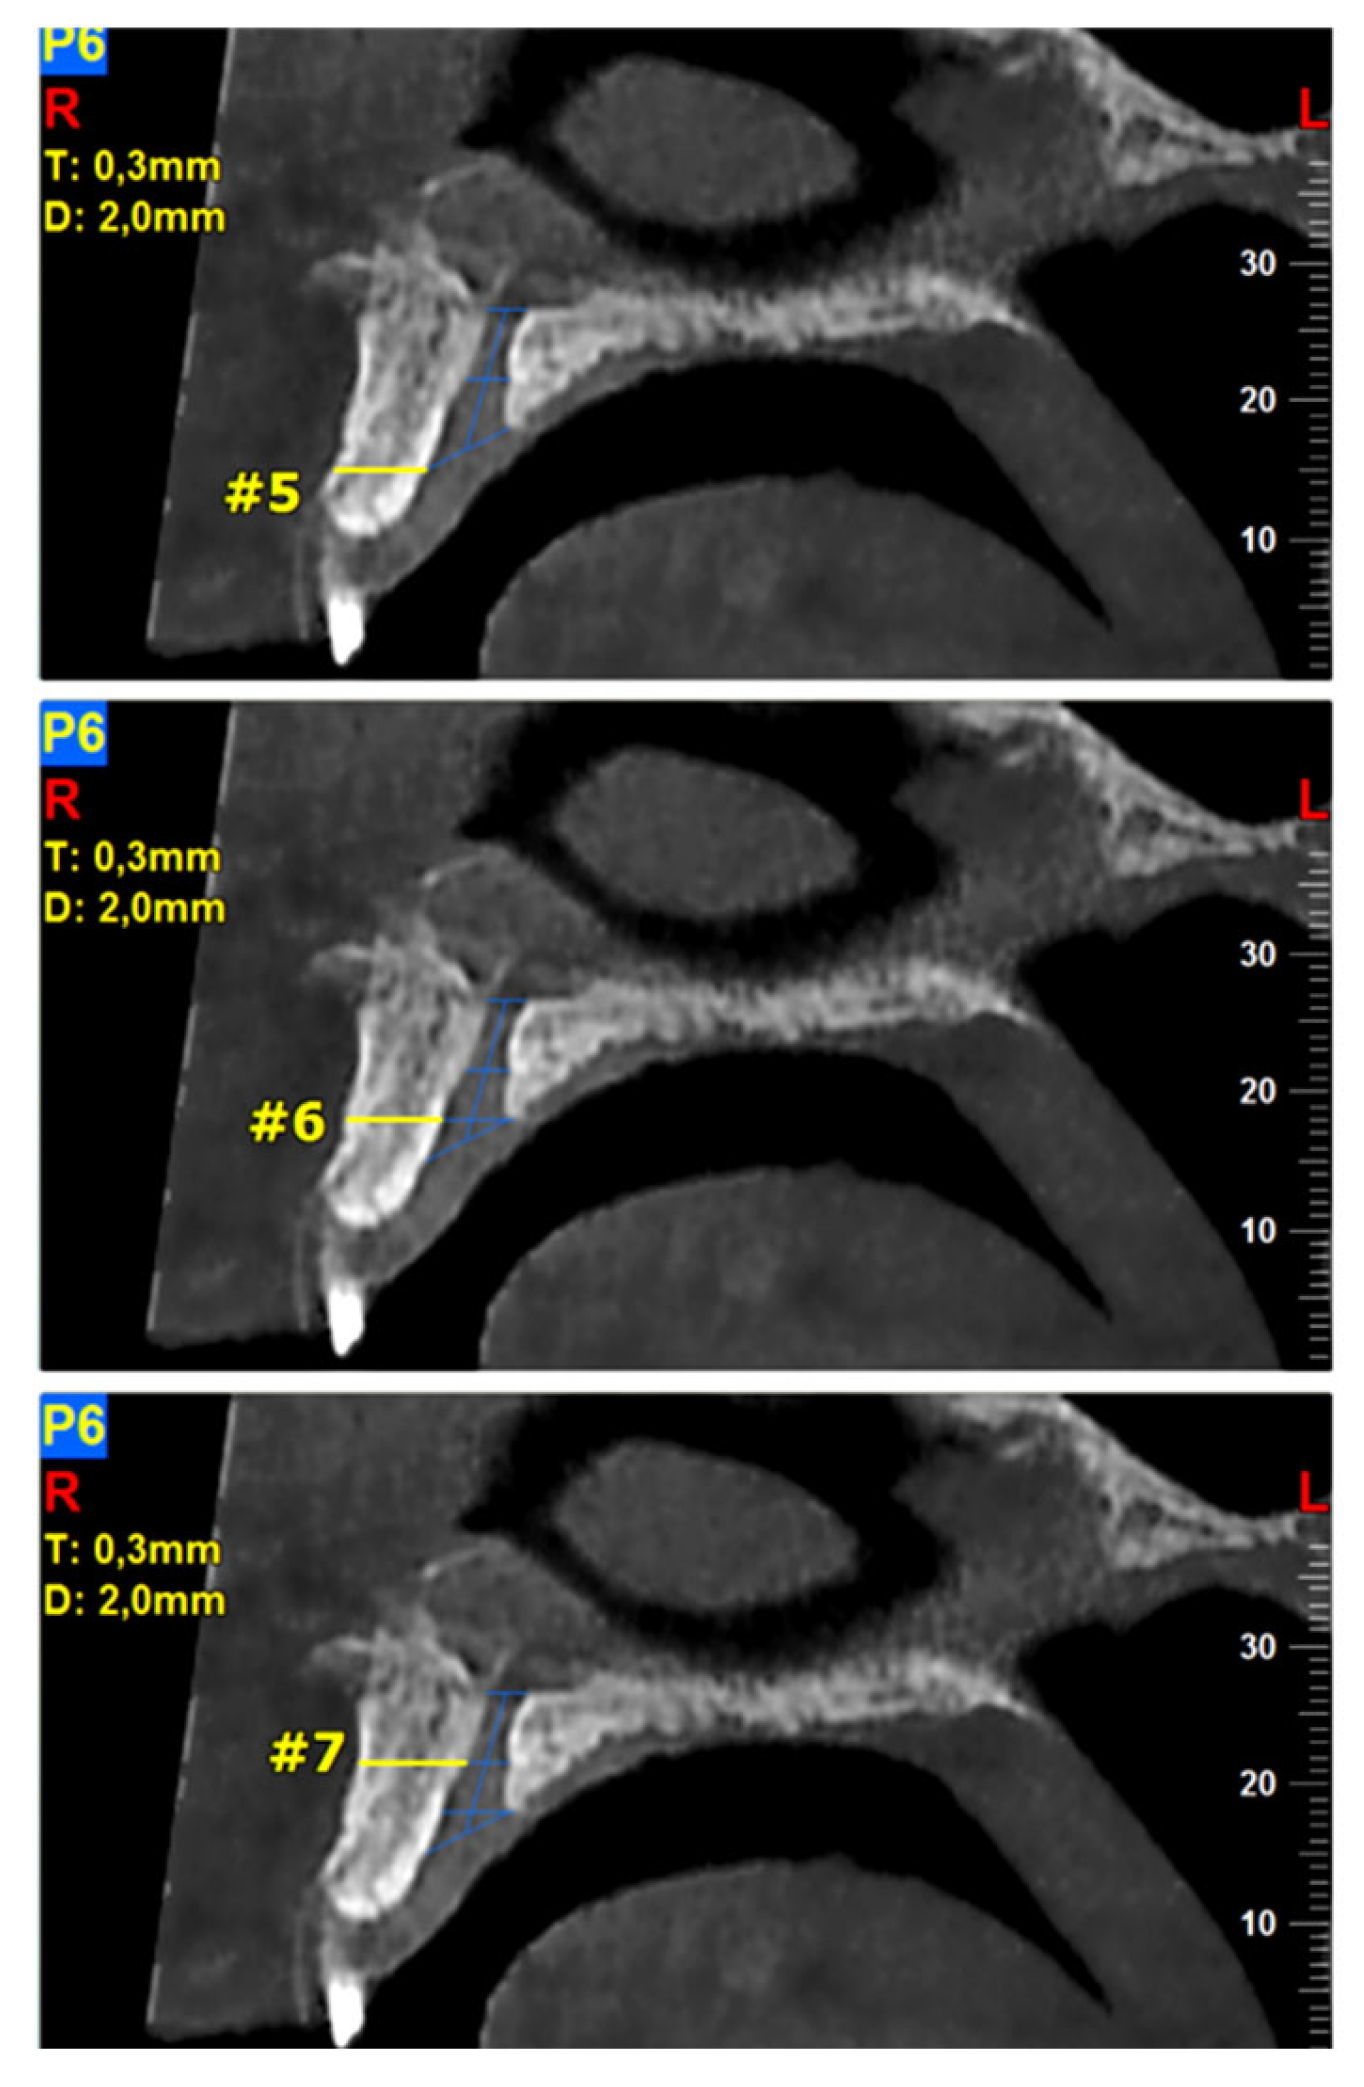

The required measurements (in mm) were: (#1) the diameter of IF, (#2) the diameter of SF, (#3) the diameter in the middle of the NPC, (#4) the total length of the NPC, (#5) the crestal distance from the buccal border of the IF to the facial aspect of the BOP, (#6) the distance midway from the buccal bone wall of the NPC to the facial aspect of the bone wall, using a horizontal line from the palatal border of the IF, and (#7) the most cranial distance from the buccal border in the middle of the NPC to the facial aspect of the buccal bone wall. These were measured on the reconstructed sagittal CBCT images (Figure 1 and Figure 2). All measurements were performed using the manufacturer’s specialized computer software (NNT v.6.2, Verona, Italy) [6,27,28]. Anatomical types of NPC were also recorded and classified as: a single canal (A), two parallel canals (B), variations of the Y-type of canal with one IF and two or more SF (C). This was performed on the reconstructed coronal CBCT images (Figure 3) [6,27,28].

Figure 2.

The following landmarks were selected for the buccal osseous plate (BOP) analysis of the sagittal cone beam computed tomography (CBCT) images (all measurements in mm): #5—the crestal distance from the buccal border of the incisive foramen (IF) to the facial aspect of the BOP, #6—the distance midway from the buccal bone wall of the NPC to the facial aspect of the bone wall, using a horizontal line from the palatal border of the IF, #7—the most cranial distance from the buccal border in the middle of the NPC to the facial aspect of the buccal bone wall.